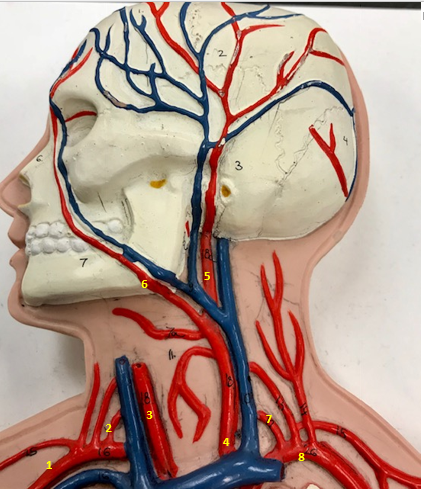

Right subclavian artery

Name #1

Supplies blood to right arm and shoulder

Function of right subclavian artery (1)

Right vertebral artery

Name #2

Supplies blood to brain and spinal cord

Function of right vertebral artery (2)

Right common carotid artery

Name #3

Supplies blood to right neck and head

Function of right common carotid artery (3)

Left common carotid artery

Name #4

Supplies blood to left neck and head

Function of left common carotid artery (4)

Left external carotid artery

Name #5

Supplies blood to face neck and skull

Function left external carotid artery (5)

Left facial artery

Name #6

Supplies blood to face and neck

Function of left facial artery (6)

Left vertebral artery

Name #7

Supplies blood to brain and spinal cord

Function of left vertebral artery (7)

Left subclavian artery

Name #8

Supplies blood to left arm and shoulder

Function of left subclavian artery (8)